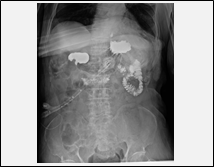

| 訪問レントゲン撮影により、次のような撮影が可能になります。 |

骨折または骨折疑い

療養中の転倒、またその他の理由で骨折が疑われる際の撮影が可能となります。 |

胃ろう交換の手技確認

胃ろう交換手技実施後、確認のための撮影が可能になります。

※在宅での胃ろう交換等が可能になります。

※胃ろう交換後の撮影にあたっては、造影剤を使用しますので事前にご相談ください。 |